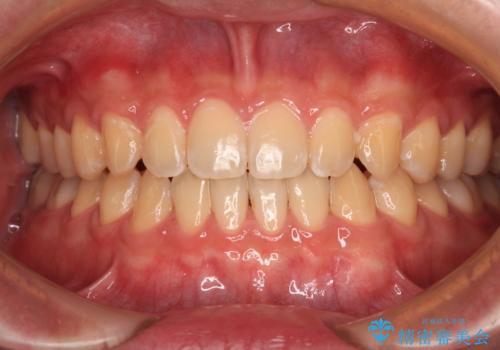

前歯のデコボコをインビザライン矯正で綺麗に改善

- 上下前歯のデコボコを気にして来院された患者様です。

全体的に叢生は軽度であったため、インビザラインにて矯正治療を行うこととしました。

舌の突出癖改善がうまくいかず、途中で舌小帯の切除を行いました。

気になる段差を納得いくまで改善させたため、治療期間は長くなりましたが、綺麗な仕上がりとなりました。